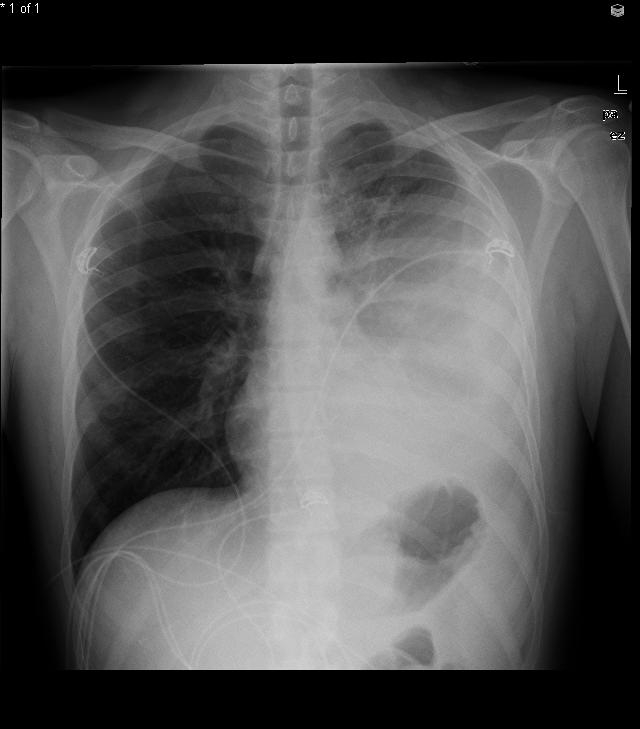

Constrictive Pericarditis

The most likely diagnosis in this patient is constrictive pericarditis, a condition marked by pericardial fibrosis and obliteration of the pericardial space. Constrictive pericarditis impairs ventricular filling during diastole, causing patients to experience symptoms related to decreased cardiac output (fatigue and dyspnea on exertion) and signs of venous overload (elevated JVP, ascites, and pedal edema). Kussmaul's sign, defined as lack of the typical inspiratory decline in central venous pressure, and the presence of a pericardial knock (early heart sound after S2) may also be seen. Sharp x and y descents are characteristically seen on central venous tracing. Pericardial calcifications can sometimes be seen on chest x-ray and, when present, help confirm the diagnosis.

In developing countries and endemic areas (eg, Africa, India & China), tuberculosis is a common cause of constrictive pericarditis. In the United States, the most common causes include idiopathic or viral pericarditis (>40%), radiation therapy (30%), cardiac surgery (10%), and connective tissue disorders.